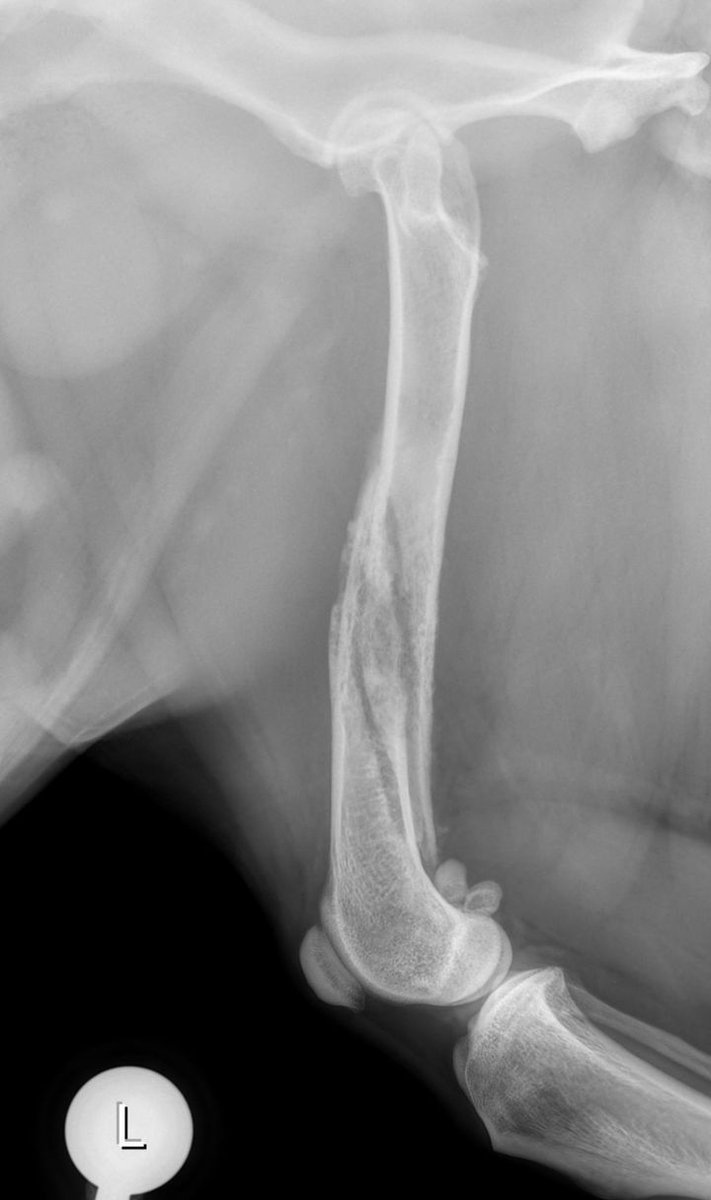

2 years

An exciting case requiring a team effort. Dr Massimo Petazzoni treated a displaced torsion fracture of the femoral shaft with two orthogonal biosurgex plates featuring our well-know, patented polyaxial locking mechanism. Read more on Facebook: https://t.co/lgUpJ9xUNL